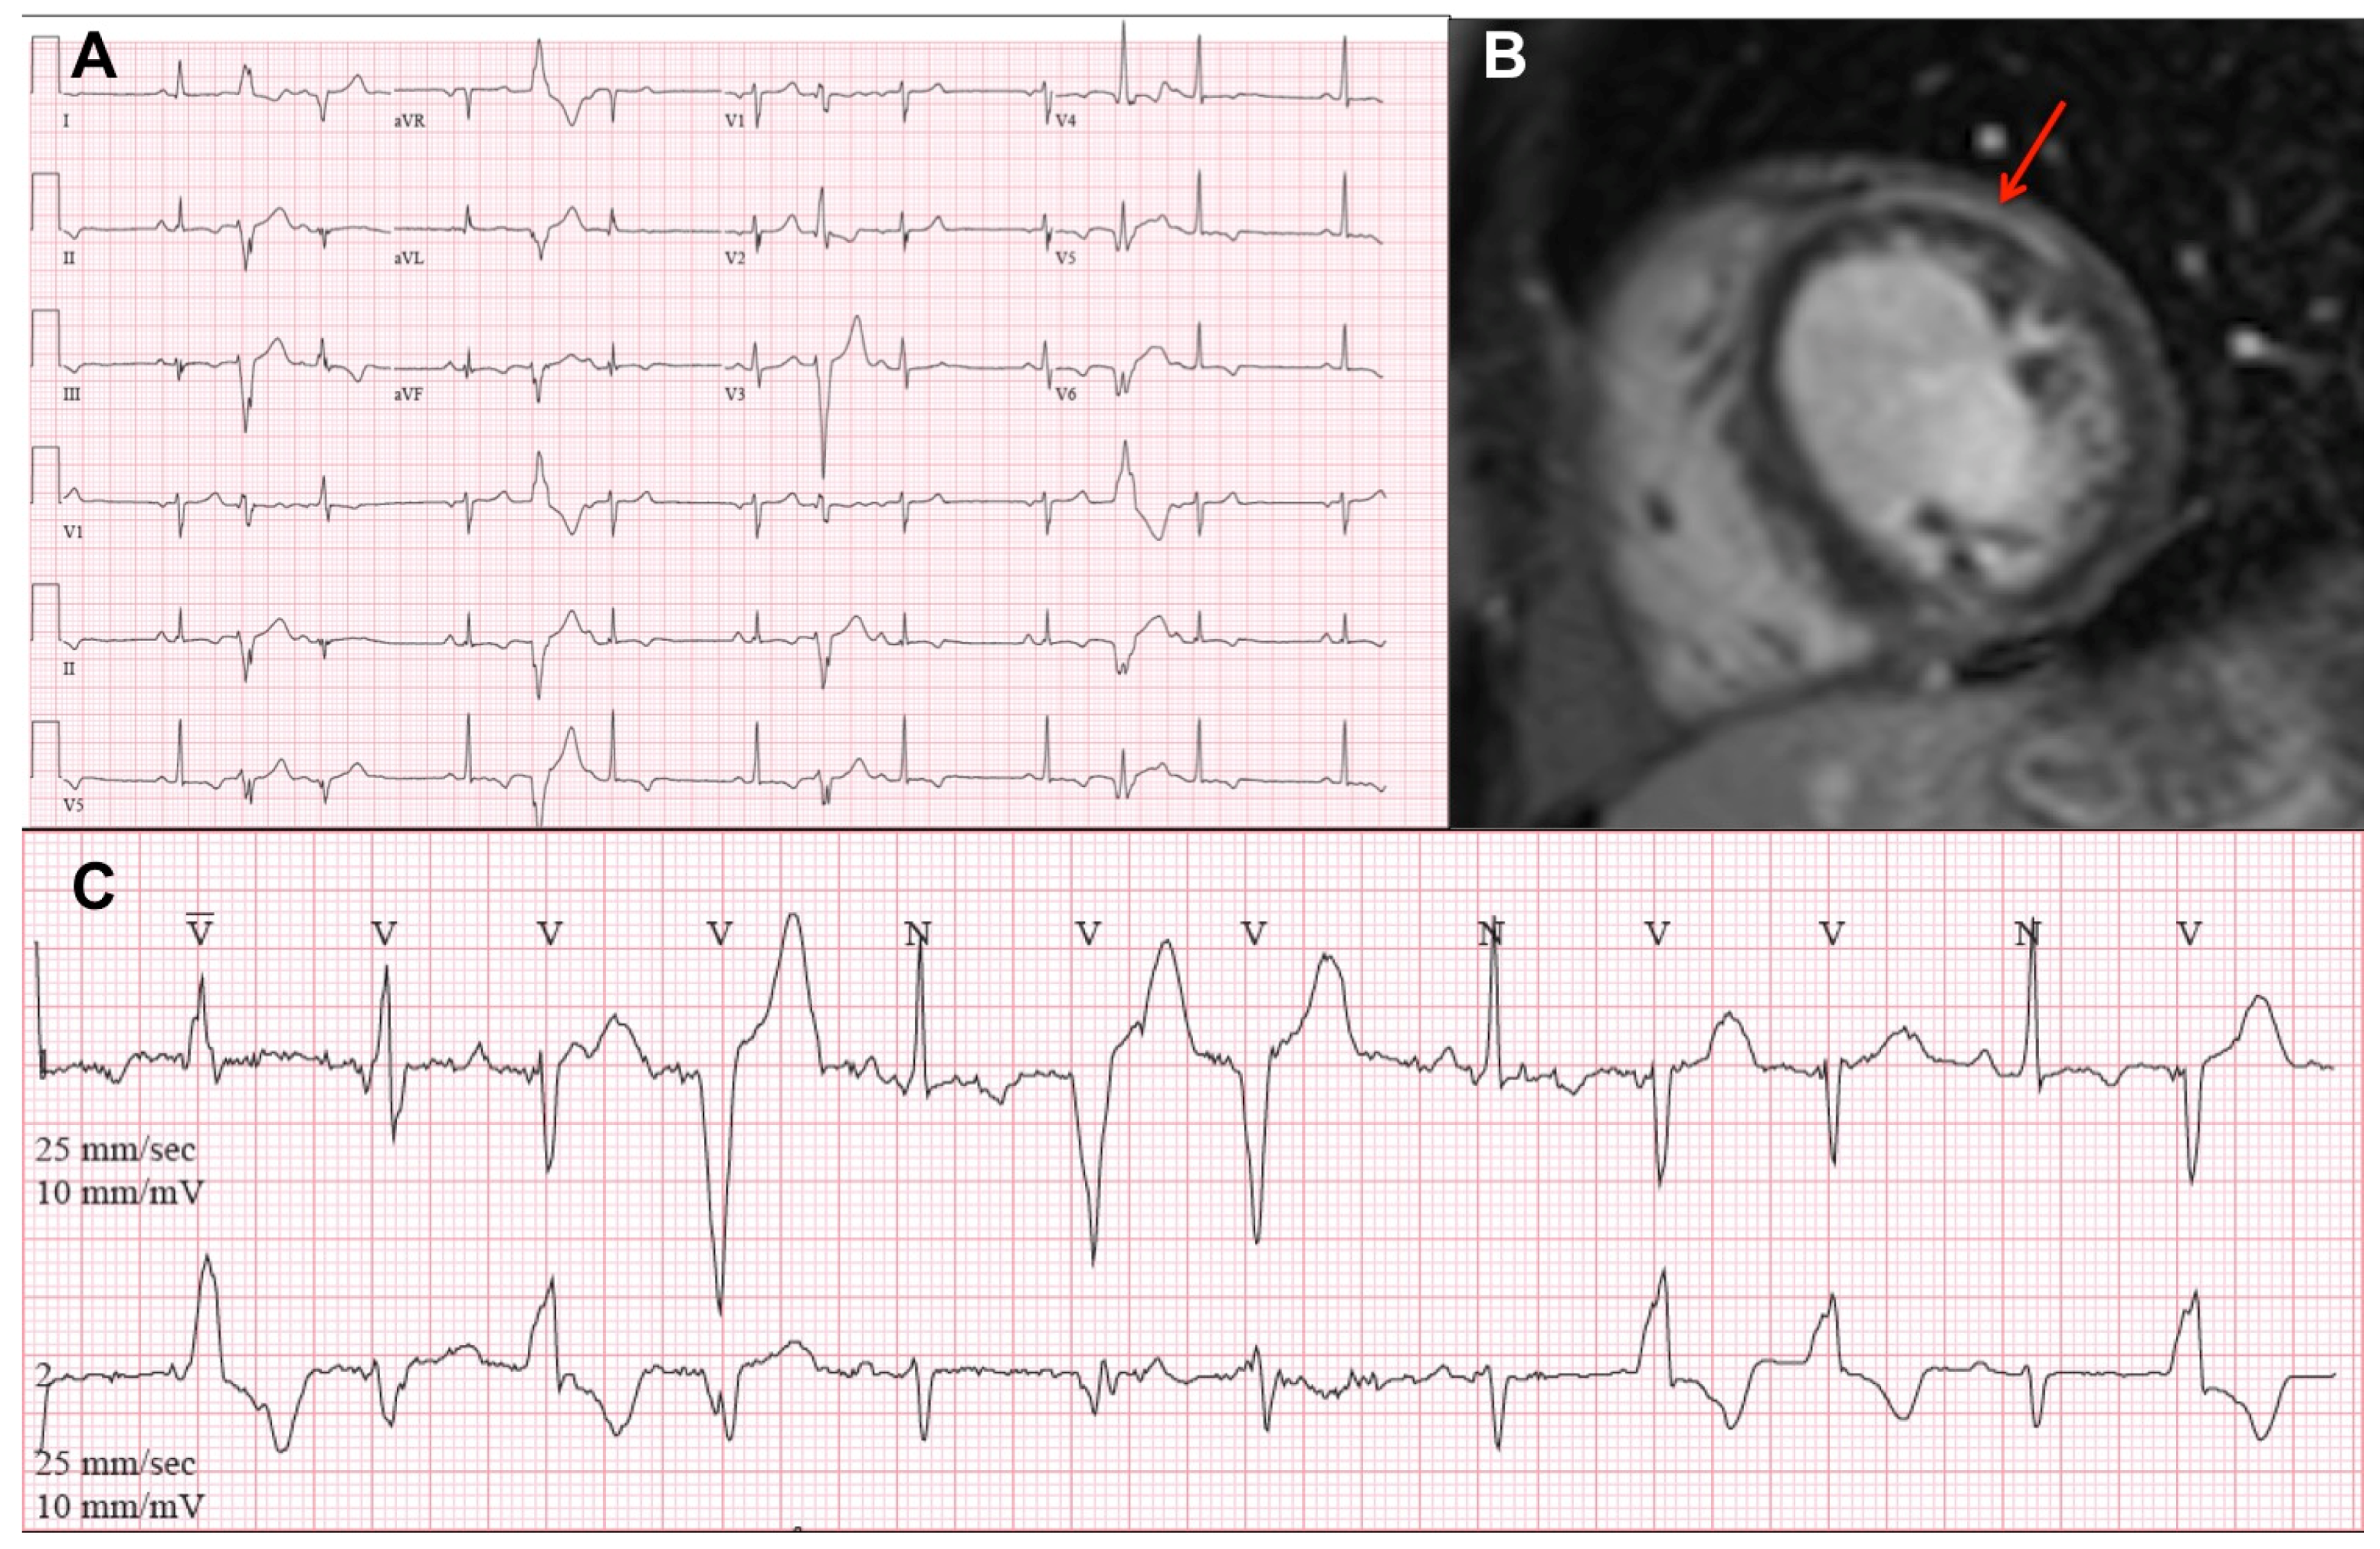

3.2. Electrocardiography and Arrhythmias

3.3. Cardiovascular Imaging